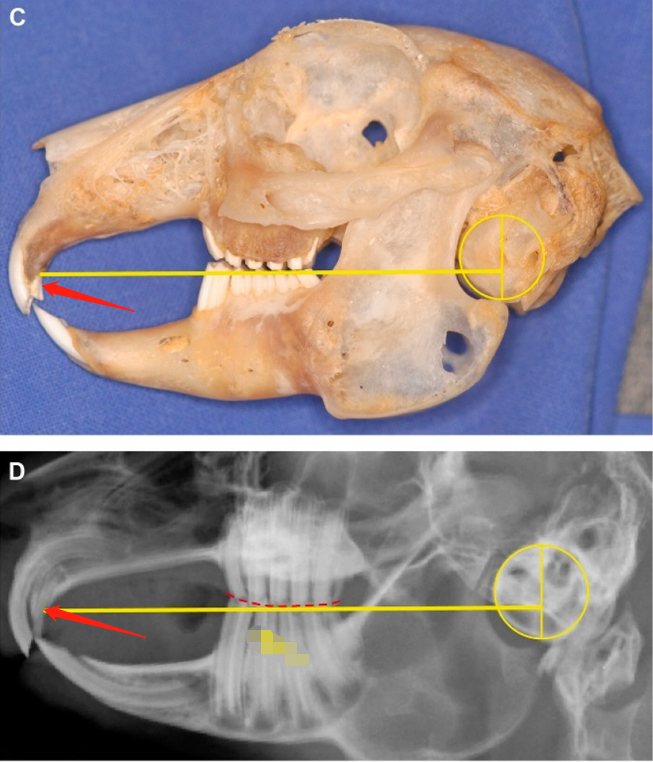

兔子牙齿过长

兔子的牙齿系列(一)兔牙齿基础